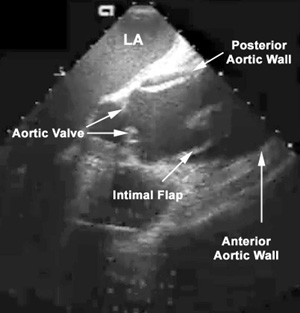

• The most definitive finding in diagnosing an aortic dissection by echocardiography involves visualization of an undulating intimal flap in the aorta.

• This intimal flap should be seen in more than one view, and should have a defined motion that is not parallel to the motion of any other cardiac or aortic root structure.

Echocardiogram

A redundant intimal flap is seen moving in the enlarged ascending aorta to the left of (superior to) the aortic valve in this patient with dissection.